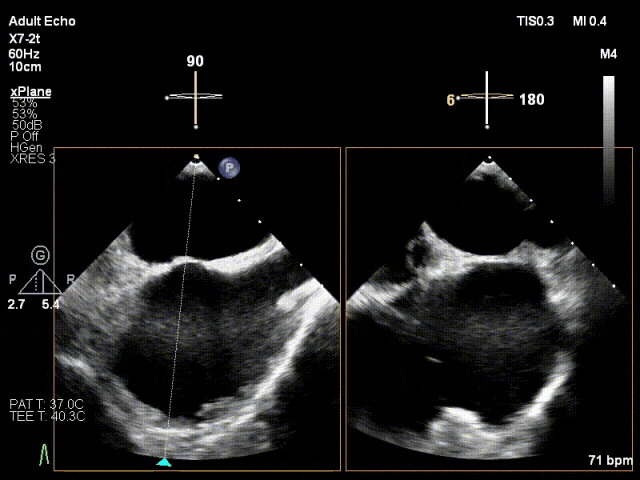

患者为41岁男性,心脏彩超提示:二尖瓣P2脱垂合并房性机制,左心扩大、瓣环扩张,反流主要来源于2区。反流宽度:20mm,2区瓣叶长度:2.2/1.3cm,AP径:43mm,瓣口面积:6.0cm²。

X-plane 2区

X-plane 2区彩色